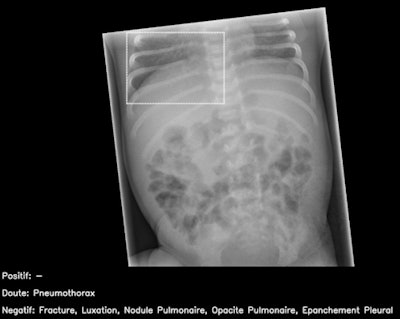

Normal pediatric abdominal radiograph interpreted by AI candidate as having right basal pneumothorax with dashed bounding box (false-positive result). This should have been identified as non-interpretable by AI. French translation: positif = positive; doute = doubt; épanchement pleural = pleural effusion; luxation = dislocation; négatif = negative; nodule pulmonaire = pulmonary nodule; opacité pulmonaire = pulmonary opacification.Allowances were made for images of body parts that the AI had not been trained in, and they were deemed uninterpretable.